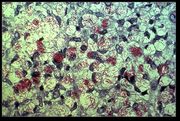

The clinical symptoms of leprosy vary but primarily affect the skin, nerves, and mucous membranes. Patients with this chronic infectious disease are classified as having paucibacillary Hansen's disease (tuberculoid leprosy), multibacillary Hansen's disease (lepromatous leprosy), or borderline leprosy.

Paucibacillary leprosy encompasses indeterminate, tuberculoid, and borderline tuberculoid leprosy. It is characterized by one or more hypopigmented skin macules and anaesthetic patches, where skin sensations are lost because of damaged peripheral nerves that have been attacked by the human host's immune cells.

Multibacillary leprosy includes midborderline, borderline lepromatous, and lepromatous leprosy. It is associated with symmetric skin lesions, nodules, plaques, thickened dermis, and frequent involvement of the nasal mucosa resulting in nasal congestion and epistaxis (nose bleeds) but typically detectable nerve damage is late.

Borderline leprosy is of intermediate severity and is the most common form. Skin lesions resemble tuberculoid leprosy but are more numerous and irregular; large patches may affect a whole limb, and peripheral nerve involvement with weakness and loss of sensation is common. This type is unstable and may become more like lepromatous leprosy or may undergo a reversal reaction, becoming more like the tuberculoid form.